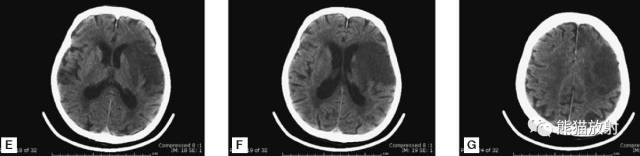

6、脑梗死

缺血性脑卒中。早期:脑水肿,灰白质分界模糊,脑沟消失;中期:病变区域密度减低;晚期:脑实质体积缩小。

A:陈旧性脑梗死,右枕叶体积缩小;

B:左枕叶急性脑梗死,灰白质分界模糊,脑沟消失;

另一患者:

C、D:亚急性期脑梗死,低密度,无明显占位效应。

左侧大脑中动脉供血区脑梗死(亚急性期):低密度,轻度水肿。

缺血性脑卒中发作2-4天时,占位效应最明显。